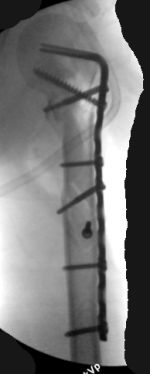

Although we can not see exactly the head piece, and assuming that there are not signs of infection, my suggestion would be to do some type of "bridging" procedure : implant fixation in head piece and distal main fragment, and the rest to be left on its soft tissue attachments (living bone graft).

I just did this attached case, using 90 degrees angled blade plate, and this would be my preference in all similar cases.

• Re: Многооскольчатый перелом плеча

Отправитель: Alexander Chelnokov 05 Октябрь 2003, 13:41

1

2

EKTE> rest to be left on its soft tissue attachments (living bone graft).

EKTE> I just did this attached case, using 90 degrees angled blade plate, and

EKTE> this would be my preference in all similar cases.

We don't even have so long plates in stock...

Well, to date he is still on abduction splint with traction applied to a wire placed through the olecranon. Images attached. The acetabulum

was ORIFed. The humerus is still discussing...

The views you now show demonstrate an extra articular fracture with good alignment on the AP, and some displacement on the lateral.

This should be able to be managed with adjustment of the traction.

Ilizarov is probably the best fixation if you decide to do so. However, it will heal with nonoperative treatment, with painless, reasonable

function. Even if it does not heal primarily, the pieces will heal enough to become a single level problem, readily solved with compression

plating. Jim Carr